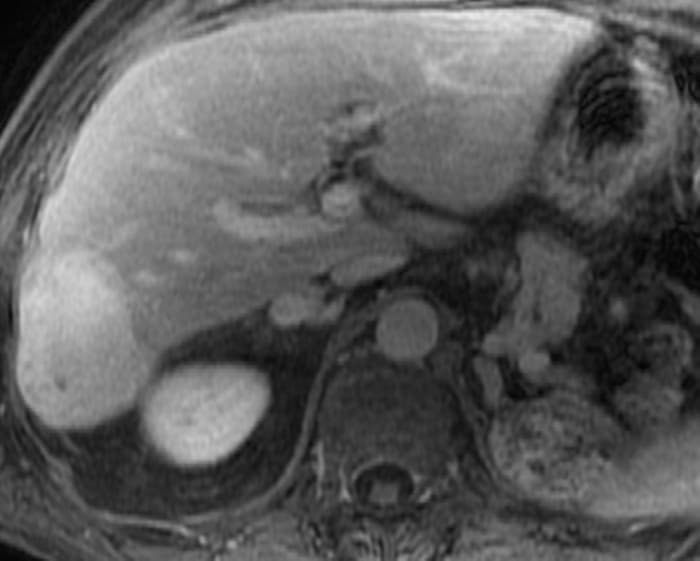

U máu gan

» Thông tin: Nam giới – 70 tuổi.

» Lâm sàng: Tiền sử ung thư thận.